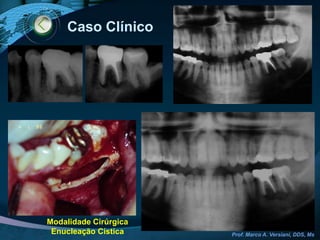

Caso ClínicoModalidade CirúrgicaApicetomia / Curetagem apical / Retrobturação